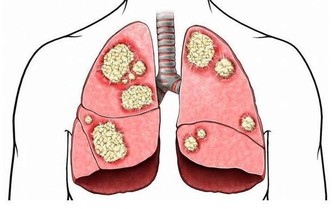

經濟高速發展帶來的嚴重霧霾污染、水體污染及食品中有害物質殘留等因素使得一些癌症,如肺癌、肝癌等的發病率呈逐年上升趨勢。現在,每年全球新發癌症的病人達一千多萬,每年死於癌症的病人超過700萬。無論哪一種癌症,我們最怕聽到的一個詞就是“晚期”,癌症發展到晚期,患者生存的希望相當渺茫,生活質量也難以保證。

目前,1/3的癌症是可以預防的,1/3的癌症是可以早期發現並治癒的,1/3的癌症是可以通過現有的醫療措施、康復治療等改善癥狀,提高患者生存質量。癌腫一旦形成,早期發現至關重要。

目前,人們更加關注腫瘤的預防與早期發現治療。如果能夠早發現癌症,以現有的醫療手段是可以大大提高患者治癒率的。

6.久治不愈的乾咳或痰中帶血,可見於肺癌。